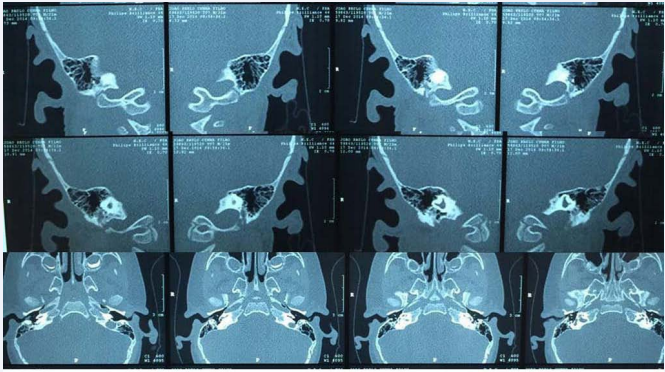

Ear CT: dysplasia of the semicircular canals and the vestibule bilaterally, amorphous content in the external auditory canal (Figure 4).

Ear CT: dysplasia of the semicircular canals and the vestibule bilaterally.

Figure 4: Ear CT: dysplasia of the semicircular canals and the vestibule bilaterally.